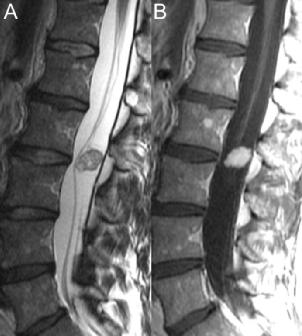

神经鞘肿瘤和脊膜瘤是髓外硬膜下的主要肿瘤。主要的神经来源肿瘤瘤为神经鞘瘤和神经纤维瘤。与胸椎相比,这些病变在腰椎中较为少见。神经鞘瘤经常影响颈椎和胸椎椎间孔内的神经根,腰椎内的神经鞘瘤也可能涉及马尾神经根。图51.1 A、B的T2和增强 T1WI分别显示了这种外观。很难区分神经鞘瘤和神经纤维瘤,即使在MRI上也是如此,尽管T2WI上的异质性外观(如图51.1中分叶状的病变)倾向于前者。神经鞘瘤也发生在神经周围,倾向于压迫而非扩大神经,更常见的表现为囊性变性,且倾向于单发而非多发。

▲ 图51.1